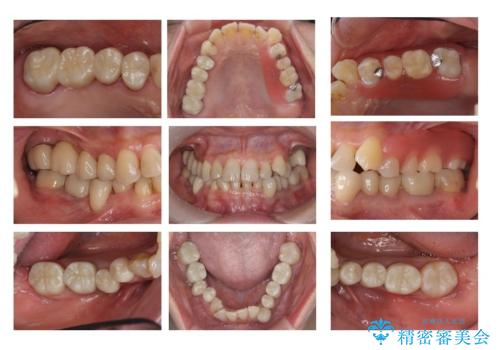

全体をきちんと治したい